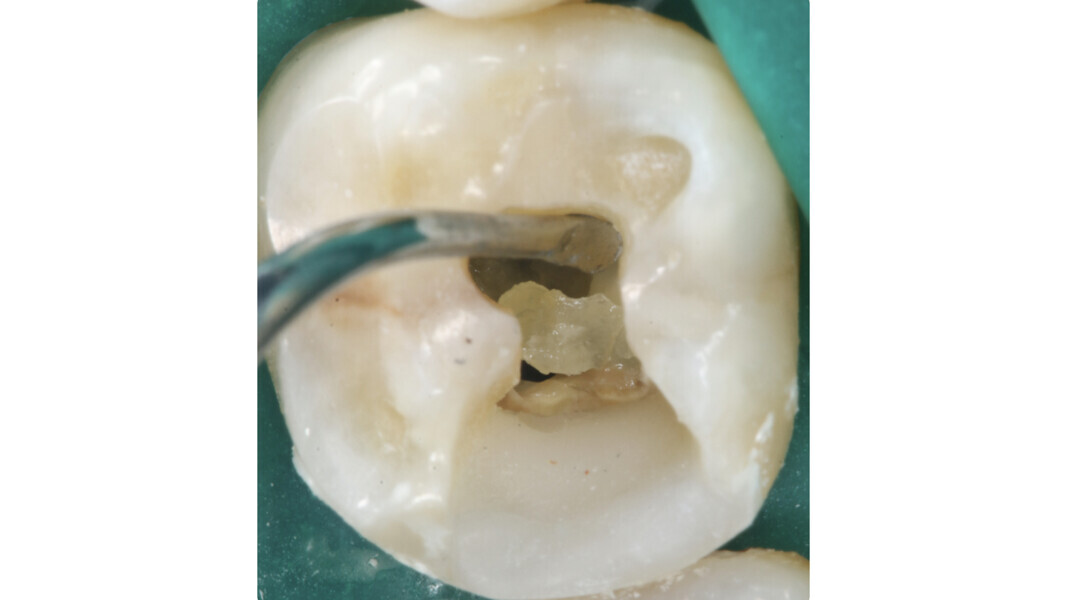

Fig. 2: Image of the access cavity prepared, showing excess removal of healthy tissue in the mesiobuccal and apical direction.

Fig. 3: Large residual pulp stone completely obstructing the palatal canal.